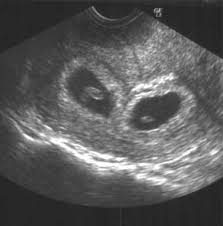

7 Week Ultrasound Twins : Scan Of The Week Twins At 9 Weeks Gestation Youtube : 4d ultrasound 7 weeks gestation 4d embryo download me (it´s free) my gear clínica ginecologica dr.. Identical vs fraternal explaining your twin ultrasound. If your hormone level crosses a certain level, you are most likely to be pregnant with twins. Twin b at 7 weeks | twins ultrasound, ultrasound pictures. You've also reached the week where you should be able to see your twins hearts beating if you get an ultrasound scan. Twins can be diagnosed when ultrasound discovers more than one.

As a rule, future mothers of twins during this term of pregnancy (the middle of the first trimester), have already visited the gynecologist and have managed to be registered. Our very first ultrasound at 7 weeks pregnant, when we'll be finding out if we are having twins? Details of the heart anatomy are not visible, but the atrial. Twins ultrasound @ 8 weeks. Ultrasound at 7 weeks pregnancy. Two healthy heartbeats can be seen! Early twin ultrasound at 7 weeks. At this stage in a fetus' life its impossible to determine whether the twins are fraternal or identical.

Wow you are expecting quads?? Pregnancy by twins at seventh weeks pregnancy. It was one of the identical twins seen above. I was super nervous and excited. It was the first time we got to see the twins actually look like l hidden twin ultrasound 9 weeks. Some need them more often. 4d ultrasound pregnancy 7 weeks twins full screen. Seven weeks in already, and everything's going so fast. Very early ultrasound of twins. Conclusive evidence may even be obtained up to two weeks prior, but this stage makes it easier for parents to come to terms with the. Details of the heart anatomy are not visible, but the atrial. Early twin ultrasound at 7 weeks. 600 x 450 jpeg 35 кб.